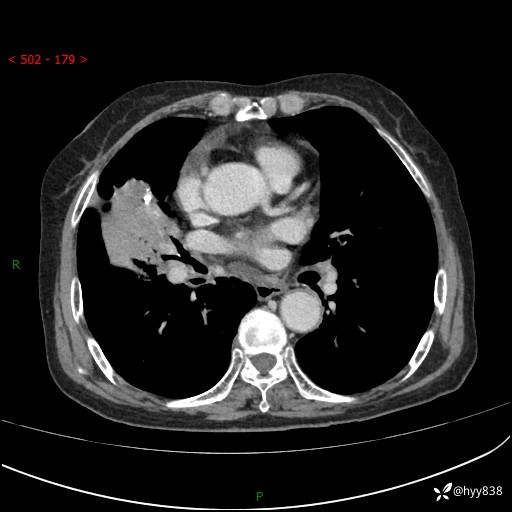

胸部CT增强(外院平扫)